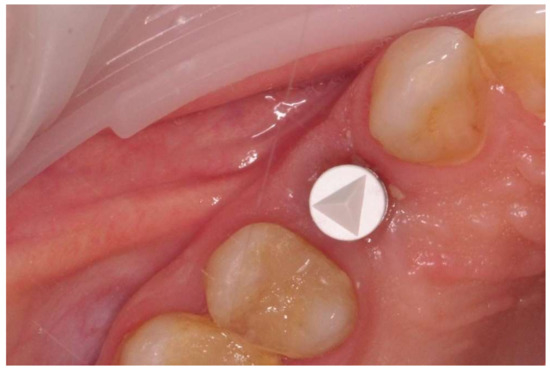

2.4. Surgical Phase

Figure 1. Implant with the healing abutment placed in bicuspid region and left for open healing.